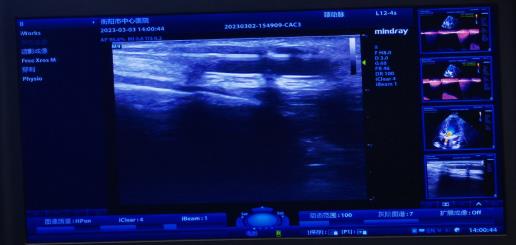

腎內(nèi)科通訊員黃佩君報(bào)道:來自衡陽縣的謝奶奶2年前因尿毒癥開始行維持性血液透析維持生命,1周前內(nèi)瘺流量明顯下降,不能滿足透析需要,慕名來到我院腎內(nèi)科就診。彩超檢查提示內(nèi)瘺口至內(nèi)瘺口近心端有約2.5cm管腔狹窄,經(jīng)綜合評估后,腎內(nèi)科陳鐵領(lǐng)副主任、彩超室王勝利副主任醫(yī)師、腎內(nèi)科王靜醫(yī)師給予患者實(shí)施彩超引導(dǎo)下動靜脈內(nèi)瘺狹窄球囊擴(kuò)張術(shù),短短20分鐘便完成手術(shù),術(shù)后患者內(nèi)瘺震顫明顯,流量大幅增加。

動靜脈內(nèi)瘺球囊擴(kuò)張術(shù)(PTA),通俗地講就是在超聲引導(dǎo)下,通過經(jīng)皮穿刺血管,置入導(dǎo)絲,沿導(dǎo)絲將高壓球囊送至血管狹窄/栓塞病變處,然后使用壓力泵打開球囊,將狹窄/栓塞的病變擴(kuò)張開的過程。它的優(yōu)勢非常明顯,不僅手術(shù)創(chuàng)面小(無切口,僅為一穿刺點(diǎn)),失血少,安全有效,可反復(fù)進(jìn)行,術(shù)后即可使用,不需中心靜脈靜脈導(dǎo)管過渡,患者舒適無痛苦,最重要的節(jié)省保護(hù)了患者的血管資源,可確保透析順利進(jìn)行。是目前動靜脈內(nèi)瘺狹窄/栓塞首選治療方法。